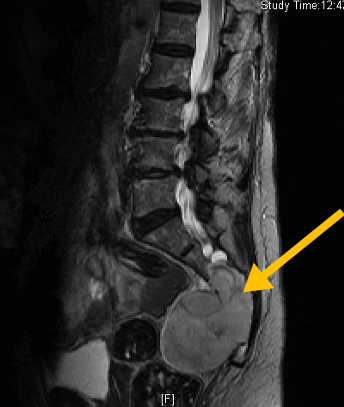

Radiographic imaging is used to help form a diagnosis of Chordoma. These include X-Ray, MRI, CT and Bone Scans.

An example of an X-ray is shown.